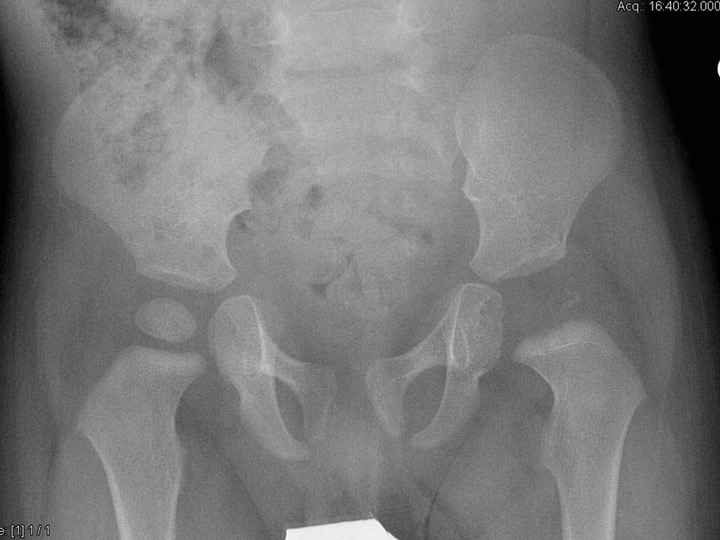

Figure 1

An 8-month-old boy sustained osteoarthritis of the left hip due to Streptococcus pneumoniae. Six months after the infection, the epiphyis had completely disappeared, confirming that children with osteoarticular infection due to S. pyogenesare more likely to have joint involvement, spread of infection into the epiphysis, and thus subsequent disturbed epiphysial growth.

Apart from K. kingae and S. aureus, other organisms causing OAI in young children include S. pyogenes and S. pneumoniae. Children with OAI due to S. pyogenes often have a previous history of varicella infection and usually present with a higher fever and white blood cell (WBC) count compared with those infected with S. aureus[1]. Children with OAI caused by S. pneumoniaeare younger than those infected with S. aureus and S. pyogenes [1, 21, 22]. They are more likely to have joint involvement, spread of infection into the epiphysis, and thus subsequent disturbed epiphysial growth (fig. 1) [1, 21, 22]. The incidence of Hib as a pathogen for OAI in young children has decreased noticeably as a result of an effective immunisation programme against this organism [1]. Hib invasive infections, such as OAI, are now rare in completely immunised children, but the onset of OAI due to Hib is not exceptional (fig. 2), considering on the other side that other serotypes are reported to cause bone and joint infections [1]. Young children with sickle cell disease have been reported to be particularly susceptible to OAI [1]. Causative organisms include Salmonella, S. aureus and, less commonly, Escherichia coli, Shigella, and S. pneumoniae.